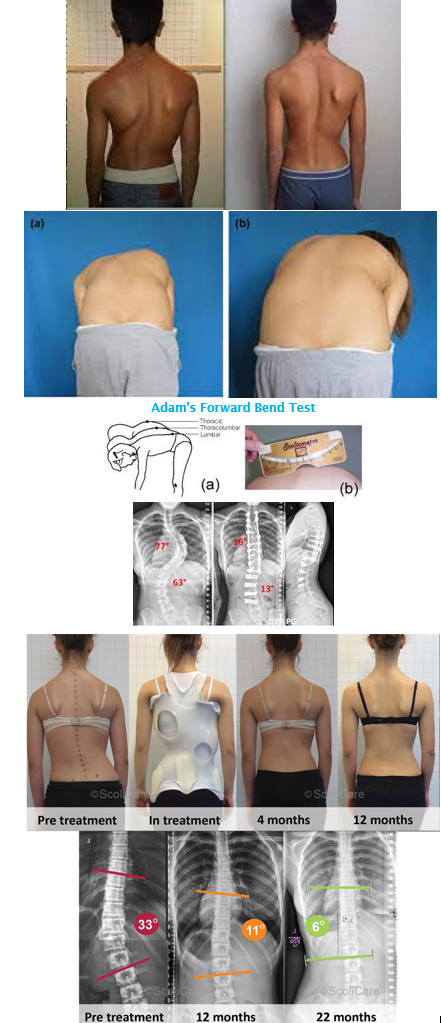

Scoliosis

Lateral curvature of the spine > 10 degrees.

If > 70 degrees, it may cause cardiopulmonary dysfunction due to alterations in the thoracic cage.

Causes:

Idiopathic (infantile, juvenile, adolescent)

Congenital (results from anomalous vertebral development)

Neuromuscular (associated with neuromuscular or muscular diseases such as cerebral palsy, myelomeningocele, spinal cord tumors, spinal muscular atrophy, and muscular dystrophies)

Screening:

Adam’s Forward Bend Test

Diagnosis:

Physical examination and full spine X-rays

Determine underlying cause (idiopathic, congenital, or neuromuscular)

Treatment:

Bracing or Spinal Fusion

Treatment depends on the degree of curvature and skeletal maturity:

If the curve is < 25 degrees, the doctor may observe the curve and repeat X-rays to monitor progression.

If the curve is between 25 and 45 degrees and the child still has growth remaining, bracing may be considered to prevent progression.

If the curve is > 50 degrees, surgery may be recommended.